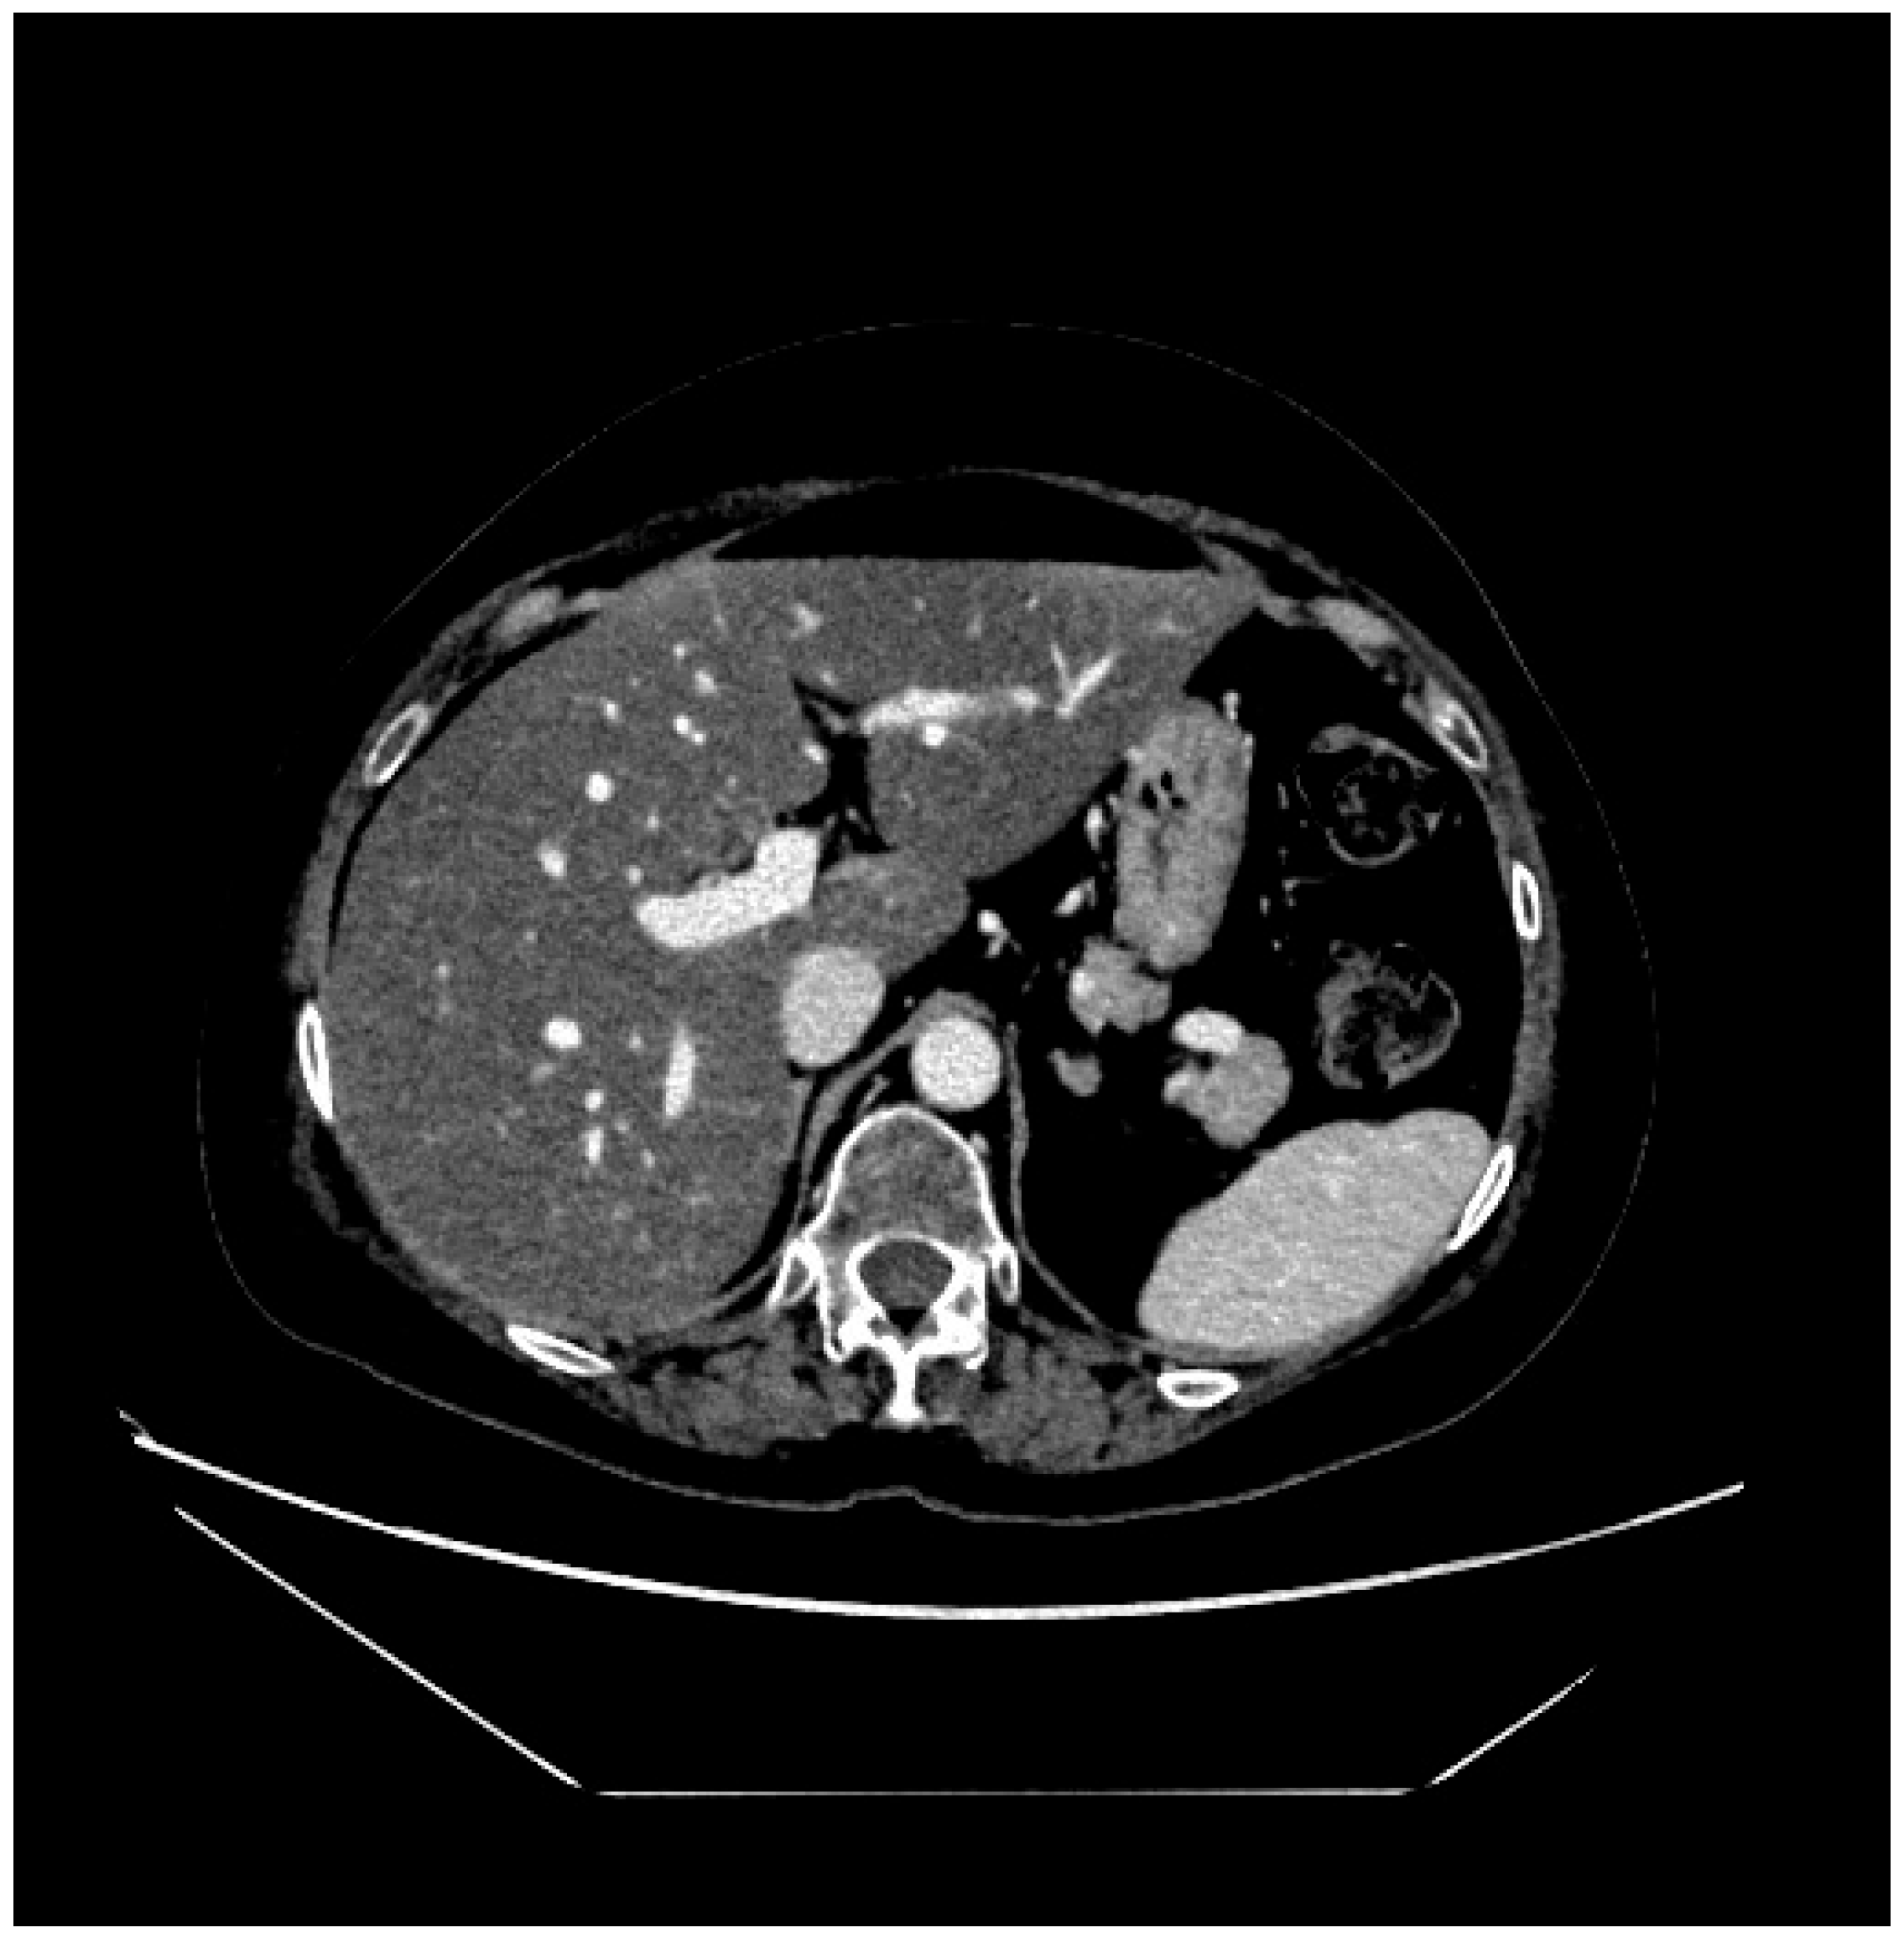

2. Case Presentation